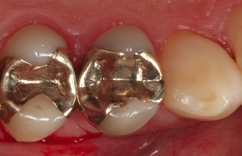

Bei dem 57-jährigen Patienten imponierte in der Routine-Bissflügelaufnahme eine Sekundärkaries an dem mit einem Gold-inlay versorgten Zahn 14 (Abb. 1). Der vitale und symptomfreie Zahn zeigte lediglich radiologisch (Abb. 2) einen Randdefekt distal sowie den Verdacht auf Karies unter dem Befestigungs- bzw. Unterfüllungszement. Nach Entfernung des Goldinlays ergab sich der Verdacht auf eine Pulpaeröffnung (Abb. 3). Klinisch war keine Blutung feststellbar, was allerdings durch die Lokalanästhesie kaschiert sein konnte. Aufgrund der Symptomlosigkeit des Zahnes und fehlender Anzeichen einer Pulpitis (fehlende Blutung) sowie einer Nekrose (erhaltene Vitalität) fiel die Entscheidung zugunsten einer Vitalerhaltung unter Beibehaltung eines engmaschigen Recalls mit Vitalitätsproben. Die Überkappung der Eröffnungsstellen erfolgte als Alternative zu Calciumhydroxid [8] mit einem Portlandzement enthaltenden Flowkomposit mit hohem pH-Wert [7,51] (TheraCal LC, Bisco, Abb. 4). Obwohl dieses Produkt hinsichtlich seiner Effektivität und Zelltoxizität nicht an ProRoot MTA (Dentsply Sirona) und Biodentine (Septodont) [42] herankommt [5,11], ist es hinsichtlich seiner Praktikabilität und der Möglichkeit des sofortigen, zügigen Weiterarbeitens konkurrenzlos. Ein vergleichbares Produkt gibt es z.B. bei Ultradent (Ultra- Blend Plus).